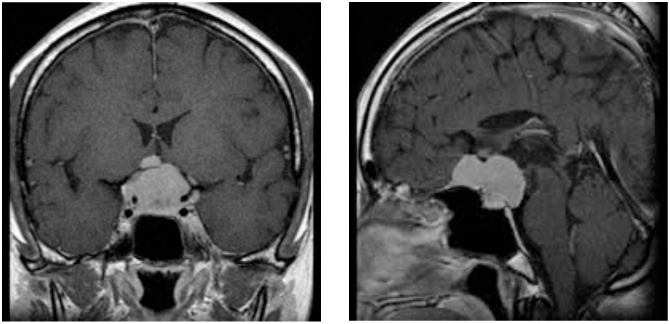

症例4

症例4は58歳。顔面の違和感で発見された小脳橋角部、テント髄膜腫である。三叉神経や外転神経、滑車神経などを巻き込む腫瘍。脳幹圧迫も強く症状は軽微であったが、腫瘍摘出を行った。後方複合錐体アプローチで一期的に神経を温存して腫瘍を摘出した。一時的に滑車神経麻痺による下方を見た時の副視が出現したが、改善している。

術前MRI 右側の脳神経を巻き込む腫瘍

神経を温存し腫瘍摘出